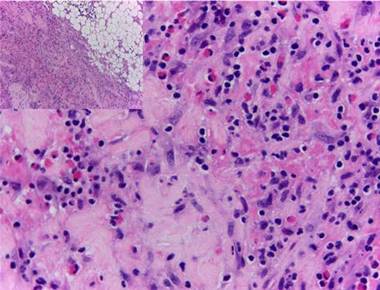

In view of the generalized commitment and the suspicion of a systemic disease, the patient was hospitalized. Among the laboratory tests performed, the blood count at admission showed a leukocytosis of 17 430 leukocytes/mm3 at the expense of eosinophils with an absolute value of 4183 (25.8%), which increased until reaching an absolute value of 5670 eosinophils/mm3 (32.8%) (Fig. 4). In addition, the patient had an erythrocyte sedimentation rate of 18 mm/h, antinuclear antibodies by indirect immunofluorescence in HEP 2 cells of 1:320 homogeneous pattern, and negative extractable nuclear antigens (Ro, La, Sm, RNP) by ELISA technique. The imaging studies included an abdominal tomography which reported hepatomegaly, as well as a tomography of the chest and a Doppler ultrasound exam, both normal. To better characterize the compromise, it was requested an MRI of the right forearm, which reported soft tissue edema affecting the entire limb and thickening of the fascia with increased uptake of the contrast agent at this level. Given these findings, the patient underwent an initial skin biopsy that included epidermis and dermis without alterations. Subsequently, a deeper biopsy was performed, in this occasion with represen tation of subcutaneous cellular tissue and muscular fascia, which demonstrated thickening of the fascia, fibrin deposi tion, and inflammatory infiltrate composed of lymphocytes and eosinophils (Fig. 5) establishing the diagnosis of EF.

Figure 5 Thickening of the fascia, fibrin deposit, and inflammatory infiltrate composed of lymphocytes and eosinophils.

The definitive diagnosis of EF is made with a skin biopsy that includes subcutaneous cellular tissue and a biopsy of the muscle fascia. The epidermis is usually not affected. In the deep reticular dermis and subcutaneous septa, it can be observed a mild inflammatory infiltrate and, in some cases, fibrosis. The main findings are at the level of the superficial fascia, where fibrosis, degenerative changes with necrosis or mucin deposit, and inflammatory infiltrate composed of lymphocytes and eosinophils can be seen. 46